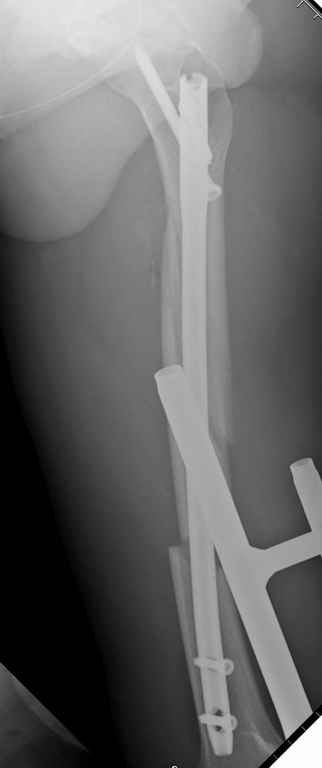

Здесь слайды случая больного с политравмой, включающей сегментарный перелом бедра и повреждение таза с нарушением тазового кольца, разрыв симфиза и перелома крестца зон 2 и 3.

На множественных слайдах важные моменты операции. Хотел бы подчеркнуть, как важно иметь возможности всех необходимых ренгенограмм, включая компютерную томографию и стандартных внутритазовых рентгенограмм (инлет и оутлет).